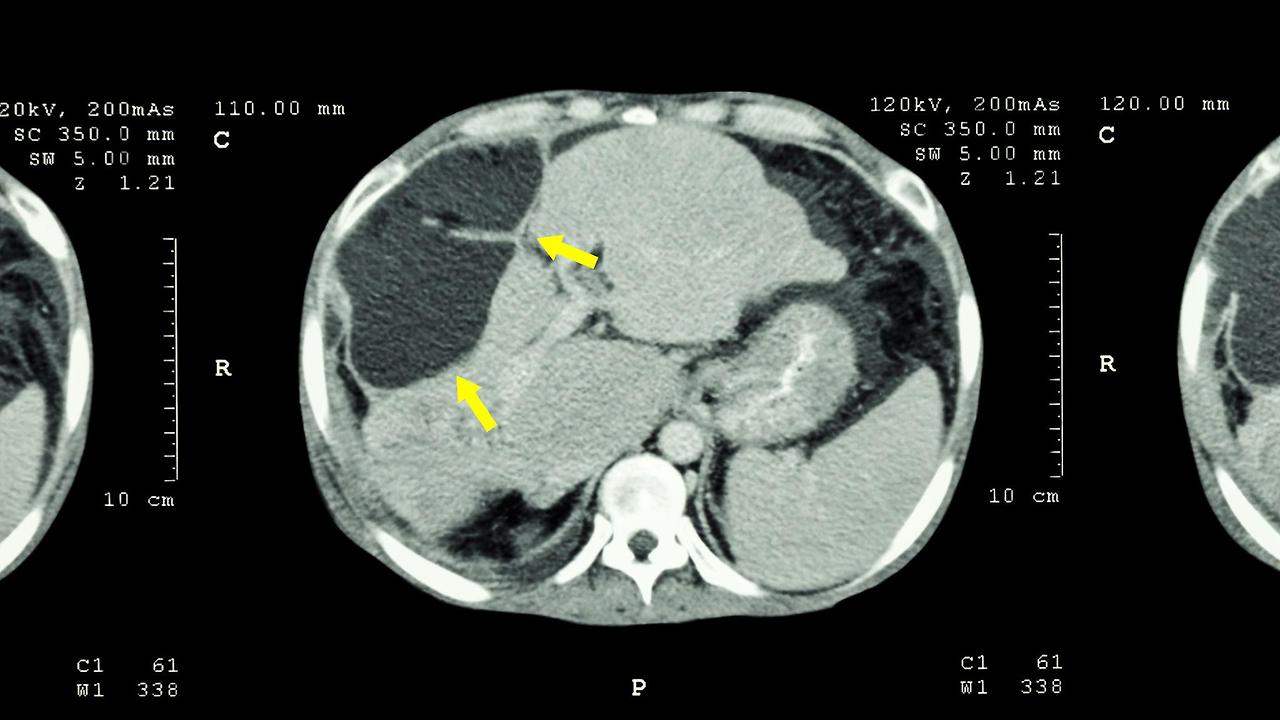

제 누나는 영상의학과 전문의인데, 일요일마다 초음파 검사 기법을 배우고 있습니다. 일반적인 건강검진용 초음파와 달리 영상의학과에서 사용하는 장비는 컴퓨터 모니터가 훨씬 크고 해상도가 높습니다. 초음파 프로브(probe)도 용도에 따라 다른데, 리니어 프로브는 유방이나 갑상선처럼 표면에 가까운 장기를 볼 때 사용하고, 커브 프로브는 복부처럼 깊은 곳에 있는 장기를 검사할 때 씁니다. 여기서 프로브란 초음파를 발생시켜 우리 몸속 장기를 영상으로 만들어주는 탐촉자를 의미합니다.

실제로 복부 초음파를 해보니 췌장을 찾는 것부터 쉽지 않았습니다. 명치 부분에 젤을 바르고 프로브를 대면 까맣게 보이는 혈관 사이로 췌장이 보이는데, 환자가 숨을 들이마시고 참는 순간을 정확히 포착해야 합니다. 장내 가스 때문에 제대로 안 보이는 경우도 많아서 숨을 내쉴 때 췌장이 잘 보이는 그 찰나의 순간을 놓치지 말아야 합니다. 실제로 한 환자분의 췌장 꼬리 부분에서 작은 이상 소견이 발견되어 대학병원에서 CT 검사를 받은 후 췌장암으로 확진된 사례도 있었습니다.

제 간을 직접 초음파로 봤을 때 충격적이었던 건, 간 전체에 기름이 껴있어서 정상보다 훨씬 밝게 보인다는 사실이었습니다. 지방간(fatty liver)이란 간세포의 5% 이상에 지방이 축적된 상태를 말합니다. 정상적인 간은 콩팥과 비슷한 명도로 보이는데, 제 간은 콩팥보다 훨씬 밝게 나타났습니다. 이는 간세포가 지방으로 대체되었다는 의미입니다.